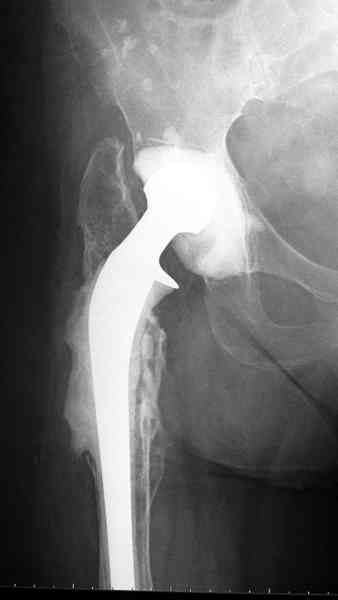

Приглашенный хирург установил ревизионный вариант бедренного компонента без замены ацетабулярного компонента, что осложнилось нагноением и свищами на уровне сустава и средней трети бедра. После двухгодичного безуспешного лечения перевязками и антибиотиками больная обратилась к нам на консультацию.

Для спейсера в бедро использовал старый длинный бедренний компонент меньшего диаметра, облепленный со всех сторон цементом с антибиотиком.

№3-6 снимки с осложнением